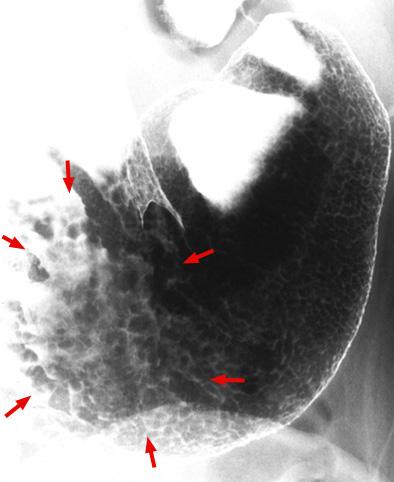

질환(병리주체)의 분류 악성 상피성종양/인환세포암

부위(장기별) 위(부위)/체부

검사방법 X-P

종양의 육안분류 0형(표재형)/IIc형(IIc)

종양의 최대경(밀리미터) 35~40

종양의 심달도 m